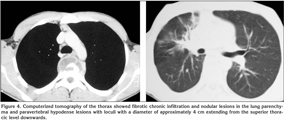

A 18-year-old Georgian male patient was admitted to the hospital with swelling above the eye, double vision, swelling and wound on the 3rd digit of the right hand. His physical examination revealed a palpable and readness mass lesion above the left eyelid (Figure 1). There was an edema, swelling and ulcerated wound on the soft tissue of the mid phalanx of the left third digit (Figure 2A). There were no relevant findings in the patient's history. A hand radiography showed the cystic appearance with expansion named "spino ventosa" in the bone tissue of the left third digit (Figure 2B). There were no abnormalities in his laboratory values. Sedimentation was 41 mm/hour. The patient underwent PPD test, which was positive. He was HIV-negative. Cranial MR was performed and a extraconal mass lesion was detected in diameter of 22 x 28 x 30 mm on the left orbita. The lesion was extending from the frontal to maxillary region (Figure 3). The lesion was localized in bone structures and subcutaneous tissue and was compressing to the left eye globe and extraocular muscles. CT of the thorax was taken, which showed fibrotic chronic infiltration and nodular lesions in the lung parenchyma and paravertebral hypodense lesions with loculi with a diameter of approximately 4 cm extending from the superior thoracic level downwards (Figure 4). Bronchoscopy revealed the edeumatous narrowing on the right upper bronchus. Acid-fast bacilli was negative by microscopic examination of bronchial lavage fluid. Excisional biopsy was performed from the mass on the patient's left eyelid and the histopathologic analysis showed "caseified granulomatous inflammation"(Figure 5). Based on the clinical, radiologic and pathologic findings, the patient was diagnosed with tuberculosis. The improvement was observed with antituberculosis treatment at lesions and symptoms of patient. The approval of patient and institution were taken to use their records for our study.

Soft tissue abscess also observed in the paravertebral area, at the anterior of the vertebral corpus, partly invading the corpus. This is defined as the initial finding of the tuberculosis spondilitis (6).